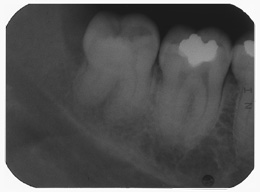

Als Zufallsbefund entdeckter, bis dahin beschwerdefreier apikaler Prozess an Zahn 36. Dessen insgesamt stark verengtes Innenraumsystem gestattete damals in erster Sitzung nur die Darstellung von 2 Kanälen. Wenn intensivstes Weitersuchen erfolglos bleibt, ist dem erfahrenen Behandler irgendwann zumindest so viel über den fehlenden Kanal bekannt: Er kann nicht sehr grosslumig sein und die Weitersuche auf den nächsten Termin zu verschieben ist nicht sehr riskant. Oft genug erlebt, gelingt dann frisch mindreseted und brainrebooted das in Sekunden, was zuvor in 20 min nicht gelingen mochte. So auch hier geschehen, bei der Suche nach dem 3. Kanal.

2 Aufnahmen sind von 2002 und die dritte vom 01.11.2010